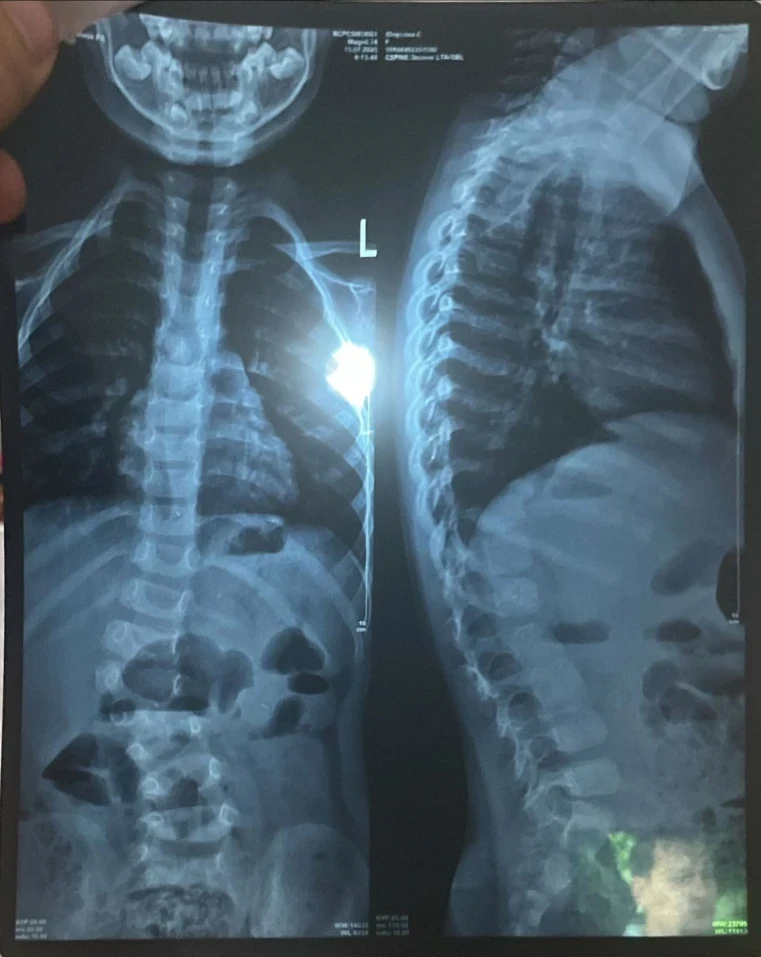

"Трудно ходить и бегать". Сумае нужна операция для исправления сколиоза

У девочки выявили сколиоз сложной формы, что вызывает у неё затруднения при ходьбе и беге, и она вынуждена проводить большую часть дня в сидячем или лежачем положении.

«Узнав, что ничего не помогает, мы обратились за консультацией к турецким профессорам. Они заявили, что единственный выход — операция, и чем быстрее она будет проведена, тем лучше для роста и развития Сумаи. Кроме того, мы узнали, что у неё есть лишняя кость на позвонке, что также является последствием сколиоза», - сообщает мама.

Сколиоз уже вызвал асимметрию тела, у Сумаи одно плечо ниже другого, а одна нога короче.

«Мы не знали, что сколиоз может привести к таким серьёзным последствиям, пока не столкнулись с этим сами. Мы проходили обследования, стараясь, чтобы дочь росла и развивалась нормально. Но о том, что искривление позвоночника может сдавливать внутренние органы и вызывать сильные боли, мы даже не подозревали. Поэтому нам нужно спешить с операцией», - добавляет Мадина.